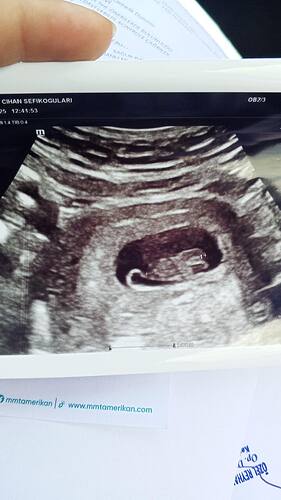

Ben kesenin fotosunu attım gözüküyor mu bilmiyorum sizce cinsiyeti bellimi

Kız gibi duruyor Allah sağlıkla kucağına almayı nasip etsin inşallah ![]()

Kız bu benim tahminim Hayırlı evlat olsun inşallah ![]()

Kız kesesi gibi duruyor sağlıkla gelsin ![]()

Sağlıcakla kucağına al canım. Bence erkek.

erkek gibi, sağlıkla gelsin bebişiniz.

@Hazalikko aşko kız gibi ama uzaktan kese fotosu var mı başka acaba